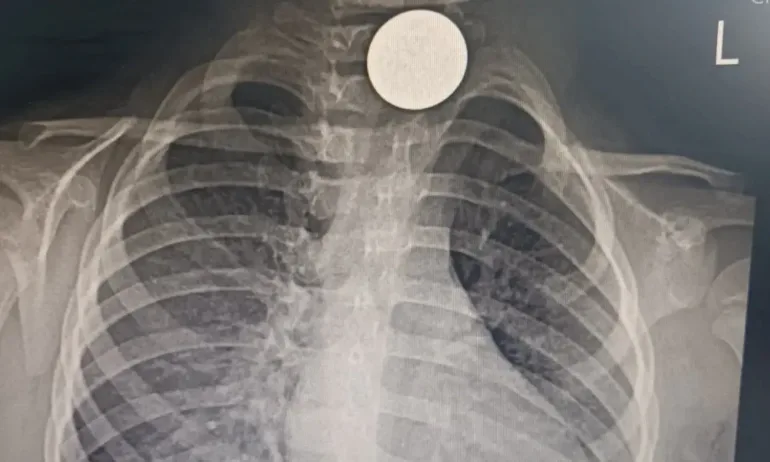

БГНЕСПреди десетина дни малката внезапно започва да вдига висока температура, а снимка на белия дроб показва монета на входа на хранопровода – в края на гърлото. Монетата е извадена в УМБАЛ Бургас от доц. д-р Даниел Петков и д-р Ивайло Илиев.

"Учудващо е как толкова дълго време детето се е хранило въпреки нея. Чуждото тяло е предизвикало хронично възпаление на хранопровода, оттам и необяснимата температура. При подобни случаи има голям риск от перфорация и сериозни усложнения, които могат да доведат дори до летален изход", посочват лекарите.